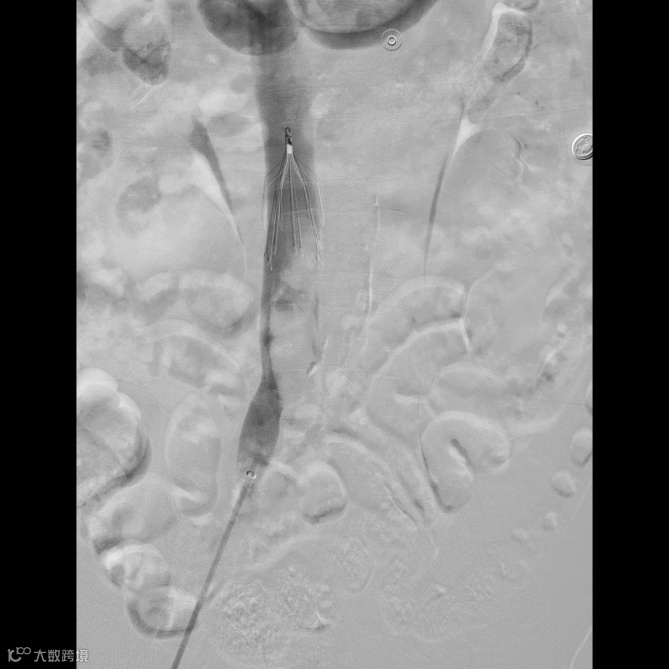

由沈阳市第一人民医院介入科陈建军主任团队运用中天天航™Pro血栓抽吸导管治疗一例急性左下肢深静脉血栓形成且伴有右下肢血流淤滞病变,成功清除血栓并快速恢复肢体灌注,欢迎大家阅读、分享、交流!

手术过程